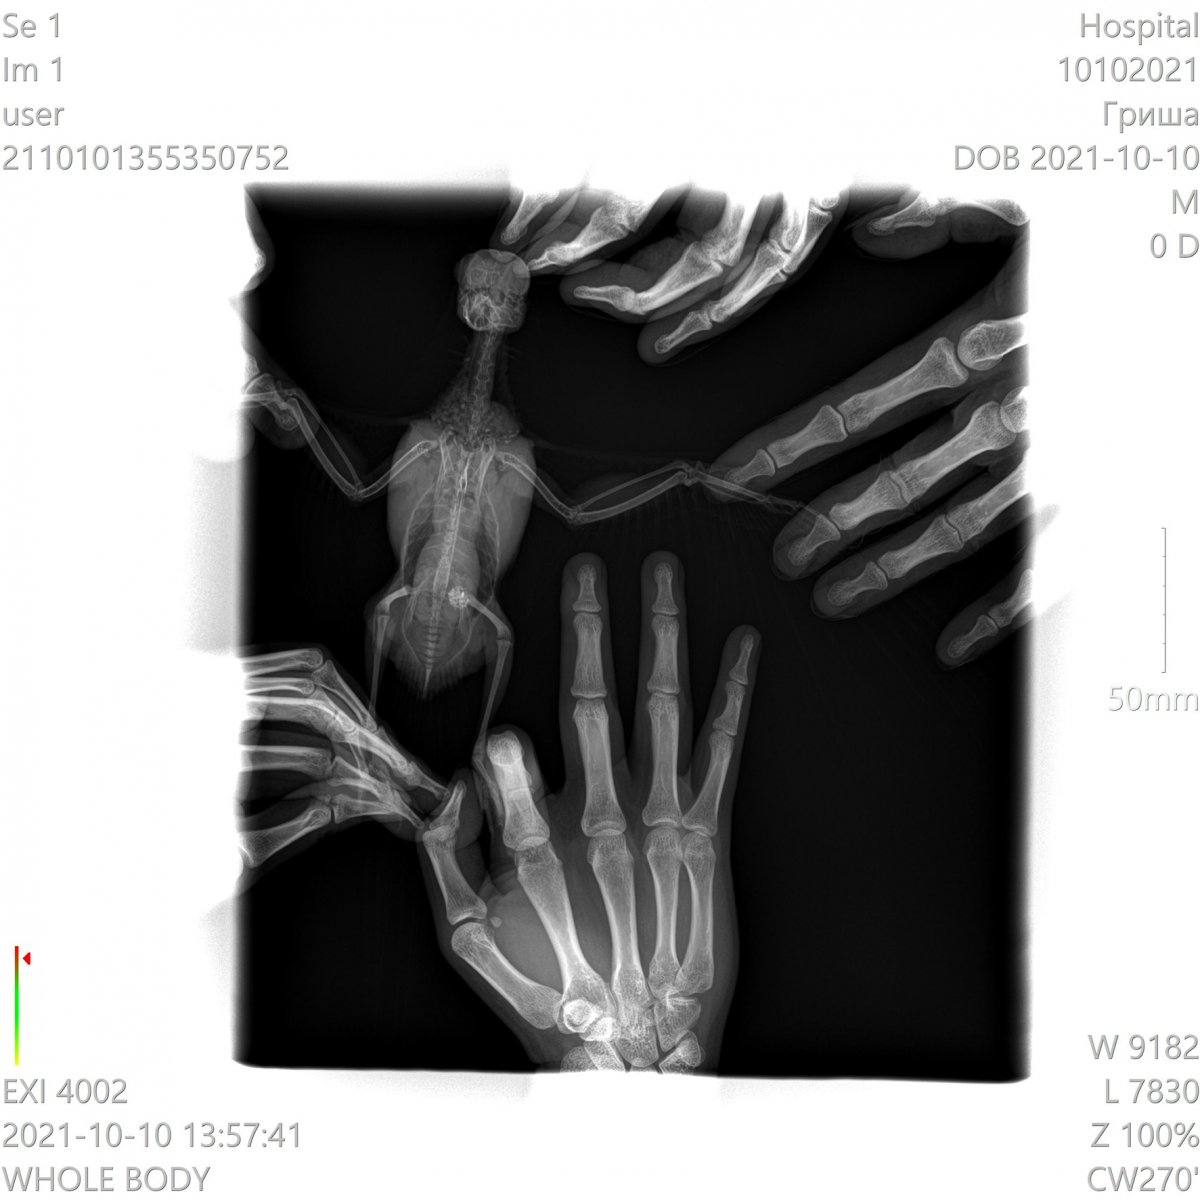

Здравствуйте, корелла самка , возраст 1 год 1 месяц. Вес 100 гр. Поведение - активная , ест, пьет. Оперение нормальное. Питание - овощи, фрукты даю, но практически не ест, каша без молочная детская, чумиза, есть копошилка, сепия, минеральный камень, скелетин с серой, бентонит кормовой, Рио для средних попугаев. Уф лампа есть , световой день 12-13 часов. Весь день летает. Взята была девочка у заводчика в возрасте 3 месяцев, заводчик настойчиво рекомендовала давать песок Рио и рисовую кашу и гречку с желтком яйца, что я и делала 4 раза в неделю, потом я выяснила, что это давать нельзя, и сразу же все убрала и не даю уже около месяца. Первые подозрения на плохое самочувствие были на постоянные вытягивания шеи, иногда трясет головой, умывается очень часто, делая при этом нервные движения при очистке Перьев. Самый основной симптом жидкий помет практически всегда. 12 августа она снесла яйцо ночью, утром я сразу же его выкинула и отвезла к орнитологу. При осмотре орнитологом она сказала , что деформированы носовые ходы , ожирение. Рекомендован был рентген, по рентгену орнитолог сказала , что к попугая : Аэросаккулит(воспаление воздушных мешков), пневмония, нефрит, гепатомегалия, повышенная плотность костей связана с гиперестрогенизмом Были сданы анализы , пока еще не готовы , один готов , вот результат: Цвет: светло-зеленый Консистенция: жидкий Соотношение микроорганизмов: подвижные кокки 50%, палочки 50%, стрептококки Кристаллы мочевой кислоты в большом количестве Нейтральный жир умеренно Билирубин отсутствует Жирные кислоты отсутствуют Соли жирных кислот отсутствуют Крахмал внеклеточный в большом количестве Крахмал внутриклеточный отсутствует Лейкоциты более 10 в поле зрения Эритроциты более 20 в поле зрения Эпителий клоаки в большом количестве Эпителий кишечный в большом количестве Слизь присутствует Дрожжи в большом количестве Простейшие не обнаружено было назначено лечение: Амоксиклав/ Флемоклав/ Экоклав (250 мг) - 1 таблетку растворить в 3 мл воды, давать / 0.2 мл, каждые 12 часов в течение месяца. Целекоксиб (200 мг) 1 капсулу растворить в 10 мл воды, давать по 0.05 мл в клюв 1 раз сутки в течение 14 дней Тербинафин таблетки 250 мг - 1 таблетку растворить в 5 мл воды, давать по 0.03 мл 1 ра в 24 часа в течение месяца. Кальций глюконат 100 мг/мл по 2-3 мл в поилку на 50 мл воды 15 дней. Гептрал/Самеликс в обычной аптеке 400 мг/5 мл по 0.1 мл в день месяц Если здесь есть орнитологи, прошу помогите пожалуйста, я была на консультации 3 врачей, я боюсь давать своей птичке Амоксиклав и тербинафин целый месяц. Не много ли это ? Как вы считаете ? И пожалуйста посмотрите рентген умоляю, скажи , что вы видите ? Насколько плохой анализ помета ? И насколько серьезны поставленные диагнозы? И возможно ли это вылечить? Остальные анализы как придут, я приложу фотографии.

Неразлучник перестал летать, когда посмотрела, обнаружила на внутренней стороне крыла шишечку, сделали рентген, фото прикладываю. Не летает, крыло отпустилось и дрожит, продолжается больше месяца, обратиться больше не к кому, у нас нет специалистов в городе. Помет у попугая не менялся, активность хорошая, кушает тоже хорошо -

Возраст: 7 полных лет. Пол: женский. Порода: сизарь обыкновенный (Columba livia). Около 4-х месяцев назад голубка перестала нести яйца. Последние две пары снесенных яиц были значительно меньше обычных (не более 2 см.). Затем (в конце июля) появились странные выделения в помете (фото 1 и 2). Такие выделения начали выходить вместе с пометом примерно 1-2 раза в месяц. Когда у нее появляются эти странные выделения она ведет себя примерно так же, как во время кладки (хвост опущен, ищет место для кладки, разгребает, учащенно дышит). В остальное время голубка жизнерадостная и активная, ест и пьет хорошо, как обычно, летает, общается и т.д. Мы были у ветеринара, ей сделали рентген (фото 3 и 4). Доктор сказала, что у нее в брюшке эти сгустки - предположительно, остатки несформированного яйца. Эти сгустки могут накапливаться и давить на органы. Доктор предложила два способа решения: Инъекция (чего именно мы не знаем). При помощи этой инъекции, предположительно, голубка должна самостоятельно избавиться от этих сгустков, которые выйдут самостоятельно. Доктор сказала, что понаблюдает за ней в течение половины дня. Оперативное вмешательство. Если инъекция не подействует - доктор сказала что нужно будет делать операцию по очистке. Но при операции есть риск неудачного исхода. В общем от операции, над инъекцией думаем. Хотим собрать мнение еще нескольких специалистов, т.к. очень боимся возможного риска и не хотим сделать хуже. Пишу сюда, потому что хочу узнать мнения людей, встречавшихся с подобными ситуациями и так же мнения орнитологов и\или голубеводов, присутствующих на этом форуме. Заранее спасибо всем за ответ!- 3 ответа

Здравствуйте! Лечу двух Гуленек - Оксаночку и Федорушку. Оксана у меня с конца июля. Лечили трихомоноз и микоплазму (не по анализам, а по симптомам, не сразу поняли, что это). Орнидазол 10 дней, пимафуцин на протяжении всего лечения + 4 дня, амоксиклав 10 дней, сумамед 14 дней. Все симптомы ушли во время лечения сумамедом. Изначально она попала ко мне с закисшими отёкшими глазками (пёрышки все были чистенькие) и слизью в горле, был запах от помёта (поэтому, возможно ошибочно, я и предположила трихомоноз) ,не всегда могла пищать, были приступы глотательных движений, во время которых слизь подступала к горлу и носу. Глазки стали проходить на амоксиклаве, но не до конца. На сумамеде всё ушло. Сейчас у Оксаночки,ттт, никаких симптомов нет. Федора у меня с 10 сентября, были наросты в горле, похожие на ранки, фото прилагаю, голоса не было, потом запах от помёта, лечила орнидазолом 14 дней, пимафуцин 14 дней. Думала голос восстанавливается, он стал лучше, но до конца не восстановился. Кроме того, когда полетает чуть больше чем пару тройку перелётов по комнате (когда мне ей лекарство надо дать, например) у неё отдышка. Дышит некоторое время с открытым клювом. Потом всё нормально, горлышко красное рыхлое. Периодически издаёт негромкий звук -пыф (как отрыжка).Бывало, кушает-кушает, потом шею вытягивает и некоторые зёрнышки вылетают. А по-началу вообще кушать трудно было ещё и из-за наростов, раздувалась вся. Наросты отпали, остальные симптомы до конца не прошли, поэтому поехали к доктору. Оксаночку даже брать не планировала, только в последний день решилась. В итоге ей, послушав обеих птиц, врач сделала рентген Оксаночке (фото прилагаю). У неё прослушались сухие хрипы с одной стороны, и жёсткое дыхание с другой. У Федоры жесткое дыхание с одной стороны, рентген не делали. Обеих пшикнули Фипристом 1 раз на кожу.Лечение тоже выписали одинаковое:1.Доксициклин (доксифин) 100мг растворить в 5мл воды,давать по 0,3мл (Оксаночке 0,28мл) внутрь - 2 раза в сутки,21 день2. Толтарокс 5% 0.15 мл (Оксане 0.14мл) внутрь 1 раз в сутки, 5 дней3.Дирофен 20 (паста или суспензия) 0,3мл внутрь, 1 раз в сутки, 3 дня4. Нистатин только Оксане прописали, но сказали, что и Федоре я могу его давать. Доктор сказала, что он транзитный, на печень не влияет,а пимафуцин не работает. На доксициклин у Оксаночки была реакция (видео прилагаю, если приложится). Спрыгнула слизь с кровью, это не симптом, такого не до не после (ттт) не было, а именно реакция на препарат. Его обеим поменяли да ципрофлоксацин. Таблетки 500мг, 1/2табл растворить в 6мл воды, 0,26 мл Оксане (она весит 280 грамм), 0,3мл Федоре (она весит 300 грамм), 2 раза в сутки Противопаразитарные на третий день (тоже обеим) отменили, т.к. Федорушку тошнило из-за них. В один из разов когда тошнило Федору, она тоже вытошлила немного слизи. Нистатин у нас не продаётся, даю Флуканозол. Капсула 50мл /5 мл воды, по 0,3 мл /2 раза в день. Сегодня 5й полный день приёма ципрофлоксацина. У Оксаночки восковица была белая до начала лечения, после доксициклина и реакции на него - порозовела. Сейчас чуть менее розовая, но не белая. Видимых симптомов у Оксаны как не было, так и нет. Федорочка «пыфает», при полётах отдышка ещё есть, но кушать стала не вытягивая шею, зерна не разбрасывает. Купила стетофонендоскоп, хочу следить за динамикой, ничего не смогла услышать. Не подскажете, как им пользоваться? Может я что-то не так делаю? Рентген у Оксаночки сильно нехороший? Ципрофлоксацин у нас дозировки в пределах нормы? Просто я по форумам полистала, везде гораздо ниже они. Сдавали пцр на микоплазму (в горветлаб спб), делали неделю, результат -у обеих нашли микоплазму. Да, у Оксаночки ещё переломы, но изначально она ко мне попала в таком состоянии, что не до них было, а потом они уже схватились.

Добрый день Не первый раз пишу сюда, обращаюсь к специалистам, модераторам. Что можно сказать по этому рентгену 14-летней розеллы (содержание условия - многократно размещала, не первая тема, птица не молода - поэтому только прошу мнение специалистов, кто может, по этим снимкам)

г.Новодвинск. Специалистов нет. Проблема: плохо ходит, падает, не ест. Помет изменился. Предположение: застревания яйца Попугай корелла самка 6 лет. Клеточное содержание. Практически без выпуска из-за собаки,детей.Неслась практически ежегодно. Корм только РИО для средних попугаев, не ограничено. Съедала много.Пила воды много. Овощи, зелень, мин.подкормка,сепии и т.п. в рационе отсутствовали. На окне в клетке в комнате. Проблемы начались в начале недели, после того как снесла яйцо. Упала с жердочки, и практически перестала ходить. Обратились к девушке волонтеру по птицам. Единственному человеку который хоть как то попытался помочь и отправил сюда. Рекомендовано: Рентген(сделан), анализы( бак.посев,копрограмма) НЕ ДЕЛАЮТ в гор.вет.лаб. Обратиться к специалисту(поэтому тут). Улучшить условия кормления и содержания(делаем). Помогите спасти птицу,пожалуйста.Ошибки осознали..исправим,но очень нужна помощь. Назначено: вазелиновое масло 0,4мл в клоаку, 0,1мл в клюв 1 раз в сутки. . Водяная баня. Кормление насильно через шприц запаренной крупой с яблочным пюре детским. Глюконат кальция ампульный по 0,05мл 1 раз в сутки, клюв. Мильгамма 1/8 таблетки в клюв. Энтеросгель 0,1мл в разведении 1:1 с водой. Нужна помощь в лечении(